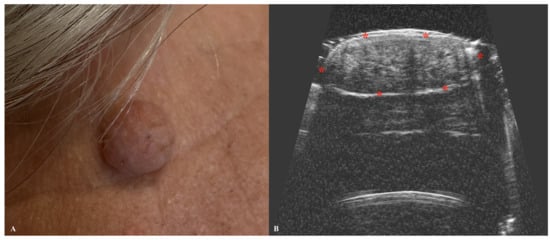

| Epidermoid Cyst | Hypoechogenic mass with well-defined borders. May show posterior acoustic enhancement. Occasionally presents mild heterogeneity. |